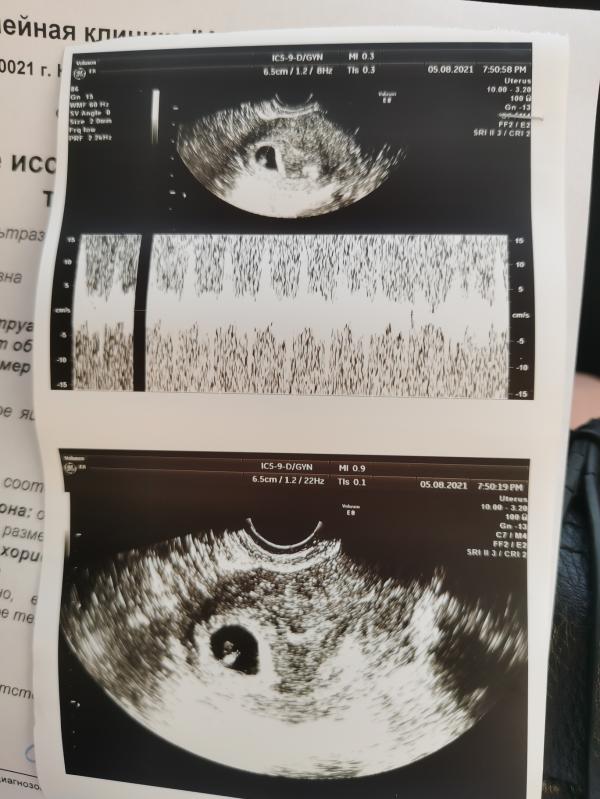

Мы маленькая креветка❤️ 6мм, ЧСС 155😍 6н 3д

05.08.2021